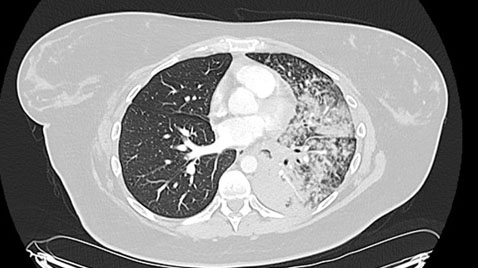

A 35-year-old Caucasian woman developed sudden onset shortness of breath and cough in June 2024, when she was 19 weeks’ gestation in her first pregnancy. Her medical history included well controlled asthma and she had undergone a right partial lobectomy as a child due to a congenital lung defect. She was a never-smoker. She was prescribed a course of oral antibiotics by her general practitioner (GP). Her cough worsened, resulting in her fracturing a rib, at which point she presented to hospital in July 2024 when she was 23 weeks’ gestation. During this hospital admission, she was initially treated for an assumed lower respiratory tract infection with antibiotics (amoxicillin and azithromycin). Routine blood tests showed a WCC 12.2 × 109/L, neutrophil count 9.2 × 109/L, and CRP 52 mg/L, a CXR showed patchy consolidation in left lower zone (Figure 3). She was positive for rhinovirus on a respiratory panel, a screen for atypical lung infections was negative, sputum microscopy culture sensitivities (MCS) negative, COVID negative, negative blood cultures. Despite antibiotics there was no clinical improvement. She went on to have a CT pulmonary angiogram (CTPA) to rule out a pulmonary embolus (PE) as a cause of her ongoing symptoms. The scan confirmed a pulmonary embolus, dense consolidation of her left lung and enlarged mediastinal lymph nodes (Figure 4). A primary lung tumor and tuberculosis were both differential diagnoses. She was commenced on treatment dose low molecular weight heparin and discharged home. Post-discharge her imaging was reviewed in a respiratory radiology meeting and a 2-week wait referral to the tuberculosis team was made.

Figure 3: CXR done on admission which revealed dense airspace opacification in left lower to midzone, as well as some mild airspace opacification in right lower zone.